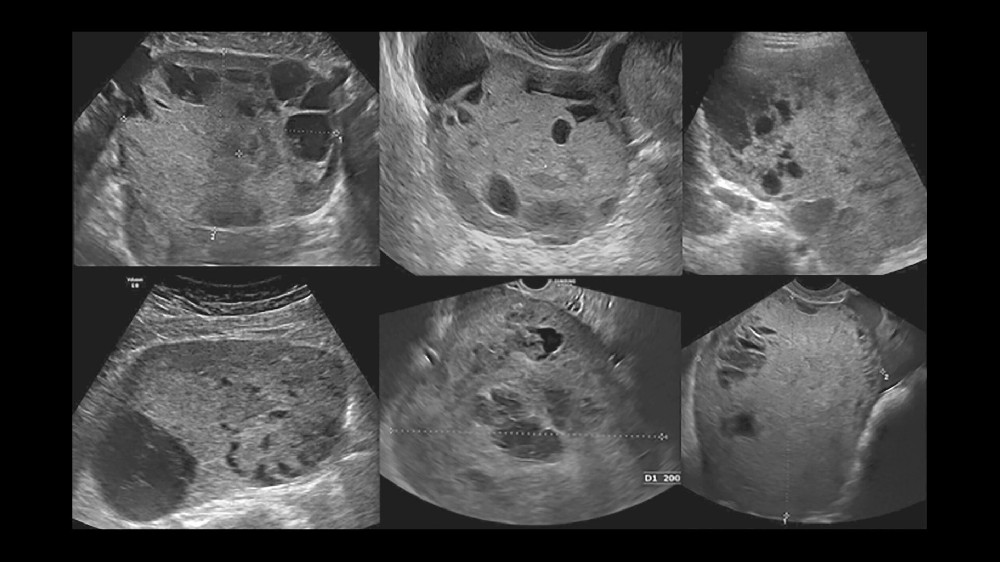

影像和活檢可提供確切證據,以進行精確的分期和治療規劃

在診斷時確定腫瘤的分期對卵黃囊腫瘤患者的存活率有關鍵性的影響。準確的分期可提供量身訂做的介入治療,提升療效並大幅改善存活機率。